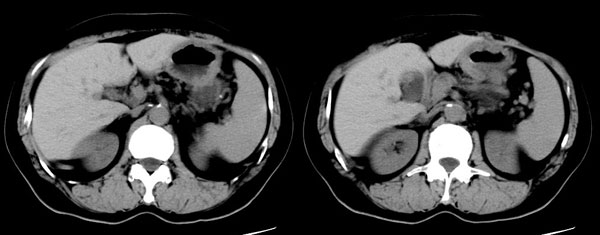

女性,58岁。卵巢癌术后4年余,无不适。体检b超发现左上腹肿块。

ct平扫加增强扫描:胆囊折叠,壁厚,其内见结石。胰腺体尾部见一5.8x7.5cm囊性肿物,ct值12hu,壁薄,增强扫描未明显强化,胰头不大,强化均匀。

ct诊断:1.胆囊炎,胆囊折叠并结石。

2.胰体尾部囊肿。